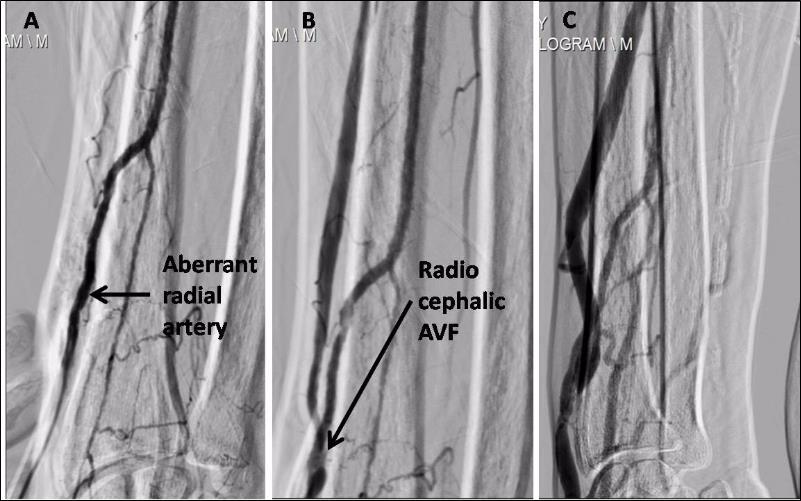

A 75 year male, known case of diabetes mellitus type 2 and hypertensionwas recently detected to have chronic kidney disease requiring hemodialysis. He was considered for arteriovenous fistula (AVF) as a long term vascular access. He was found to have bilateral anomalous radial artery. The encountered vessel coursed abnormally superficial to the tendons of the extensor pollicus brevis (EPB), abductor pollicus longus (APL) and extensor pollicus longus (EPL) lying lateral to the cephalic vein as it passed through the anatomical snuffbox. A right radiocephalic AVF was constructed with side to side anastomosis (Figure 1). AVF angiogram demonstrated an aberrant course of radial artery with well developed AVF (Figure 2). Patient is successfully undergoing hemodialysis through the same fistula since 1 year. To best of our knowledge, this is the first case of AVF with aberrant radial artery to be reported in world literature.

Figure 2.A. Aberrant course of right radial artery. It normally lies above the lateral epicondyle of radius bone, fistulogram demonstrated its course away from radius bone. B. Working right radiocephalic AV Fistula. Right cephalic vein is seen medial to the artery at the site of anastomosis and later running lateral to it. C. A well developed cephalic vein suitable for cannulation for hemodialysis.